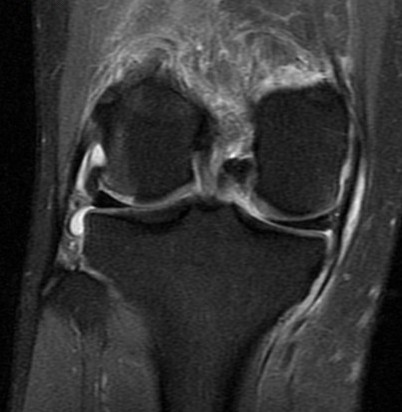

25 y/o twisting injury

Torn mid medial patellofemoral ligemnt, chondral defect of the lateral femoral condyle and medial patella. Displaced chondral fragment adjacent to the lateral femur within the lateral joint space. Also has trochlear dysplasia type B with a subtle supratrochlear spur and an increased tibial tubercle central trochlear distance.

Patellar dislocation